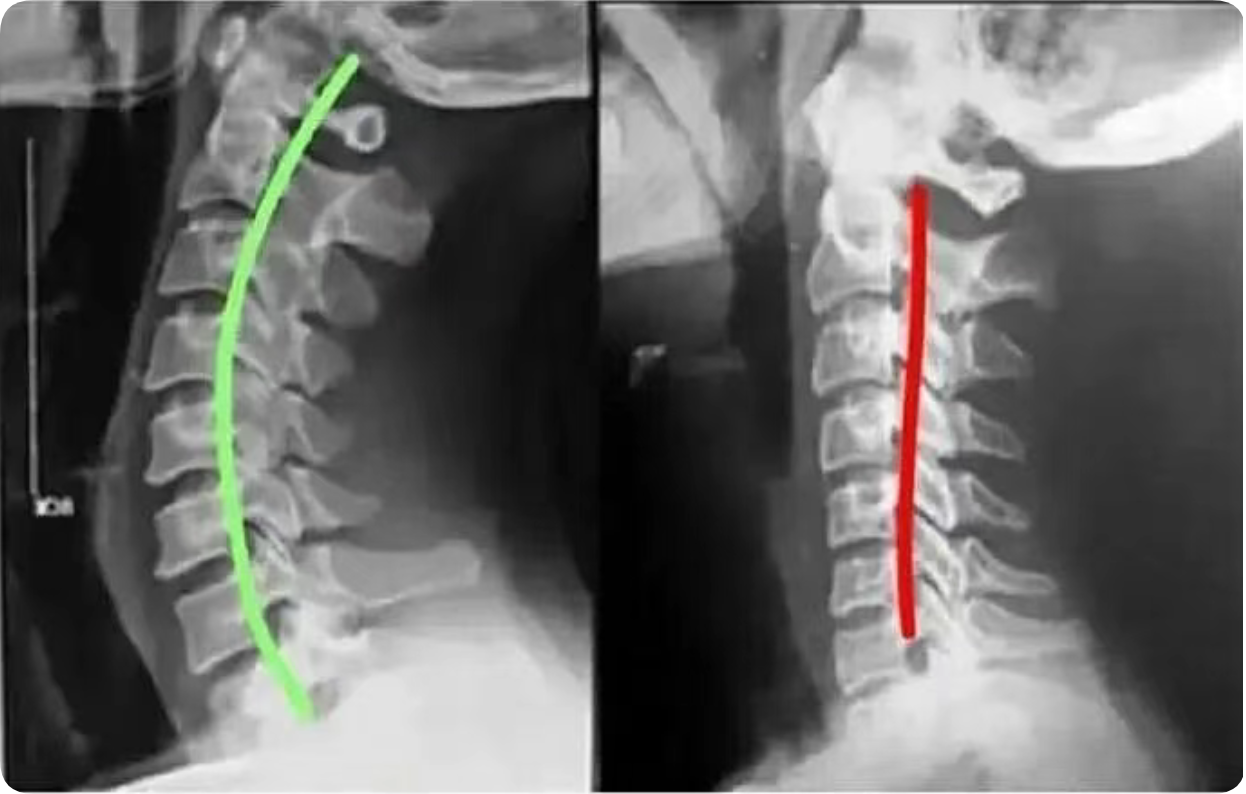

患者均有上颈段不适、头前屈后伸及颈部左右旋转受限,查体上颈段棘突有偏歪,局部压痛明显。颈椎X线检查:颈椎前后缘有骨 质增生,椎间隙变窄,生理曲度变直或颈 椎后缘连线中断、反弓;后纵韧带钙化,双线征、双突影,椎体呈仰、俯式或旋转式移 位;张口位示寰齿侧间隙及寰枢关节间隙左右不对称,寰枢椎外侧缘左右不对称, 齿状突轴线至枢椎外侧缘距离不相等,或 与寰椎的中轴线不重叠,二轴线互成夹角或分离。

手法整复,纠正了偏歪的 棘突,使错位的椎体复位,解除了对颈总 静脉、颈内动脉、迷走神经及颈前交感神 经节的压迫,解除了脑干神经核供血不 足,也解决了局部面神经供血不足,从而 达到治疗面瘫的目的;手法整复,还调整 了错位的小关节,松解了椎体周围挛缩的 肌肉韧带,消除或改善了椎体失衡状态, 恢复了颈椎力学平衡,改善了局部软组织 对血管神经的压迫,改善了局部血液循 环,有利于面瘫的回复。